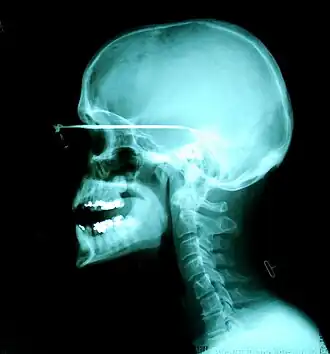

Röntgenstraling is elektromagnetische straling met een kortere golflengte dan zichtbaar licht, die vrij gemakkelijk door weefsels heen dringt en selectief wordt tegengehouden door zwaardere materialen daarin. Vooral botweefsel is vrij ondoorlaatbaar voor röntgenstraling.

Aangezien röntgenstralen zich niet met lenzen en slechts zeer moeilijk met spiegels laten bundelen, vormen röntgenopnamen meestal schaduwbeelden van een object. De röntgenstraler, het object en het voor röntgenstralen gevoelige element (röntgenfilm, fosforplaat of matrix van scintillatie- of vaste-stofdetectoren) moeten daarbij een as vormen. Het te onderzoeken voorwerp of de te onderzoeken persoon wordt voor een cassette gezet, waarin zich een onbelichte fotografische film bevindt, waarna er uit een röntgenbuis een bundel röntgenstraling op de film komt, wat afhankelijk van de straling plaatselijk meer of minder zwarting zal geven op de film. Na ontwikkeling van de film is een beeld zichtbaar van de dichtere structuren in het lichaam van de patiënt. Beenderen laten weinig straling door en blijven op de film onbelicht. Luchthoudend longweefsel wordt (op het negatief) donker afgebeeld doordat het veel straling doorlaat. Bloed, vet, spieren en organen krijgen een grijstint. Hoe meer de röntgenbron een puntbron benadert, hoe scherper de afbeelding wordt. In tegenstelling tot gewone foto's worden röntgenfoto's zelden of nooit afgedrukt; de negatieffilm wordt direct gebruikt ter beoordeling. Een orgaan of weefsel dat röntgenstraling niet doorlaat heet radio-opaak (ook wel radiopaak). Een gebied dat meer straling doorlaat dan de omgeving heet ook wel hypodens of radiolucent.